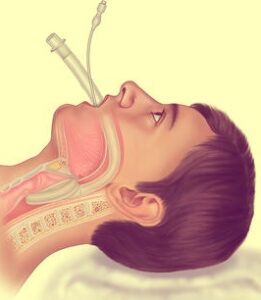

- Simple airway adjuncts: nasopharyngeal airway

Tracheal intubation in advanced life support

Laryngoscopy and intubation of the trachea should not last longer than 30 seconds. Any doubt about the correct placement of the tube in the trachea leads to tube withdrawal and re-oxygenating the patient before further attempts.